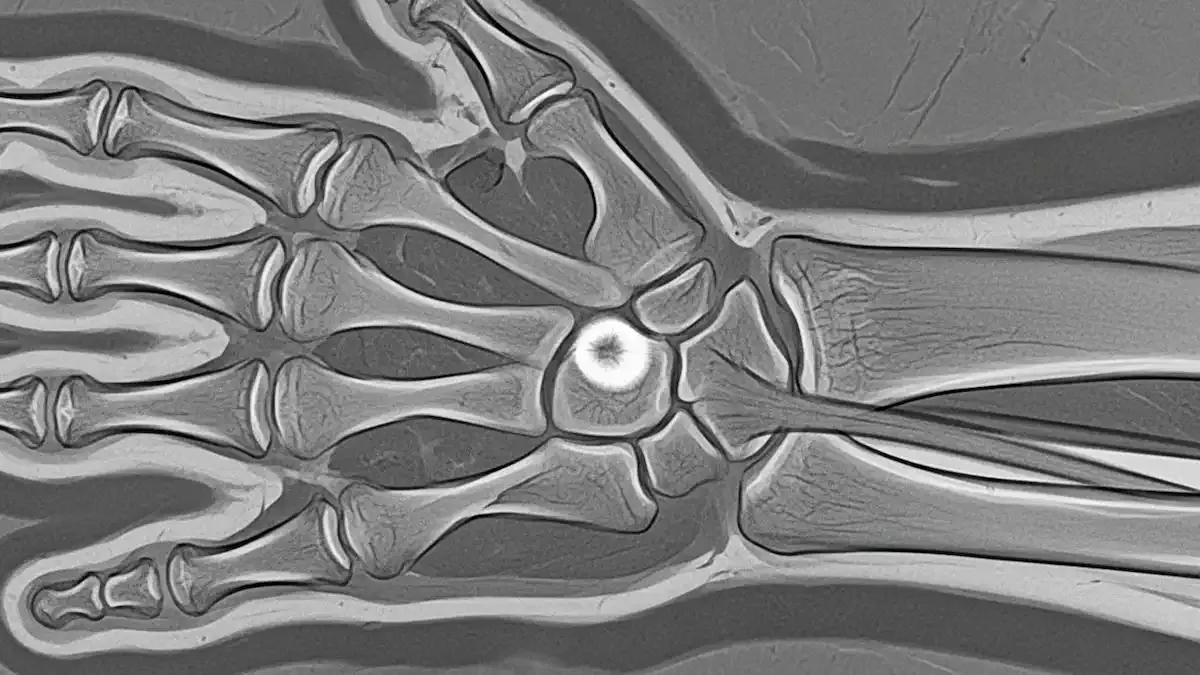

O escafoide é um dos oito pequenos ossos do carpo, localizado na região do punho, e sua importância biomecânica é fundamental para os movimentos da mão.

A vascularização peculiar do escafoide, com suprimento sanguíneo retrógrado, contribui significativamente para esta complicação, sendo a porção proximal do osso, que recebe menos irrigação, particularmente vulnerável.